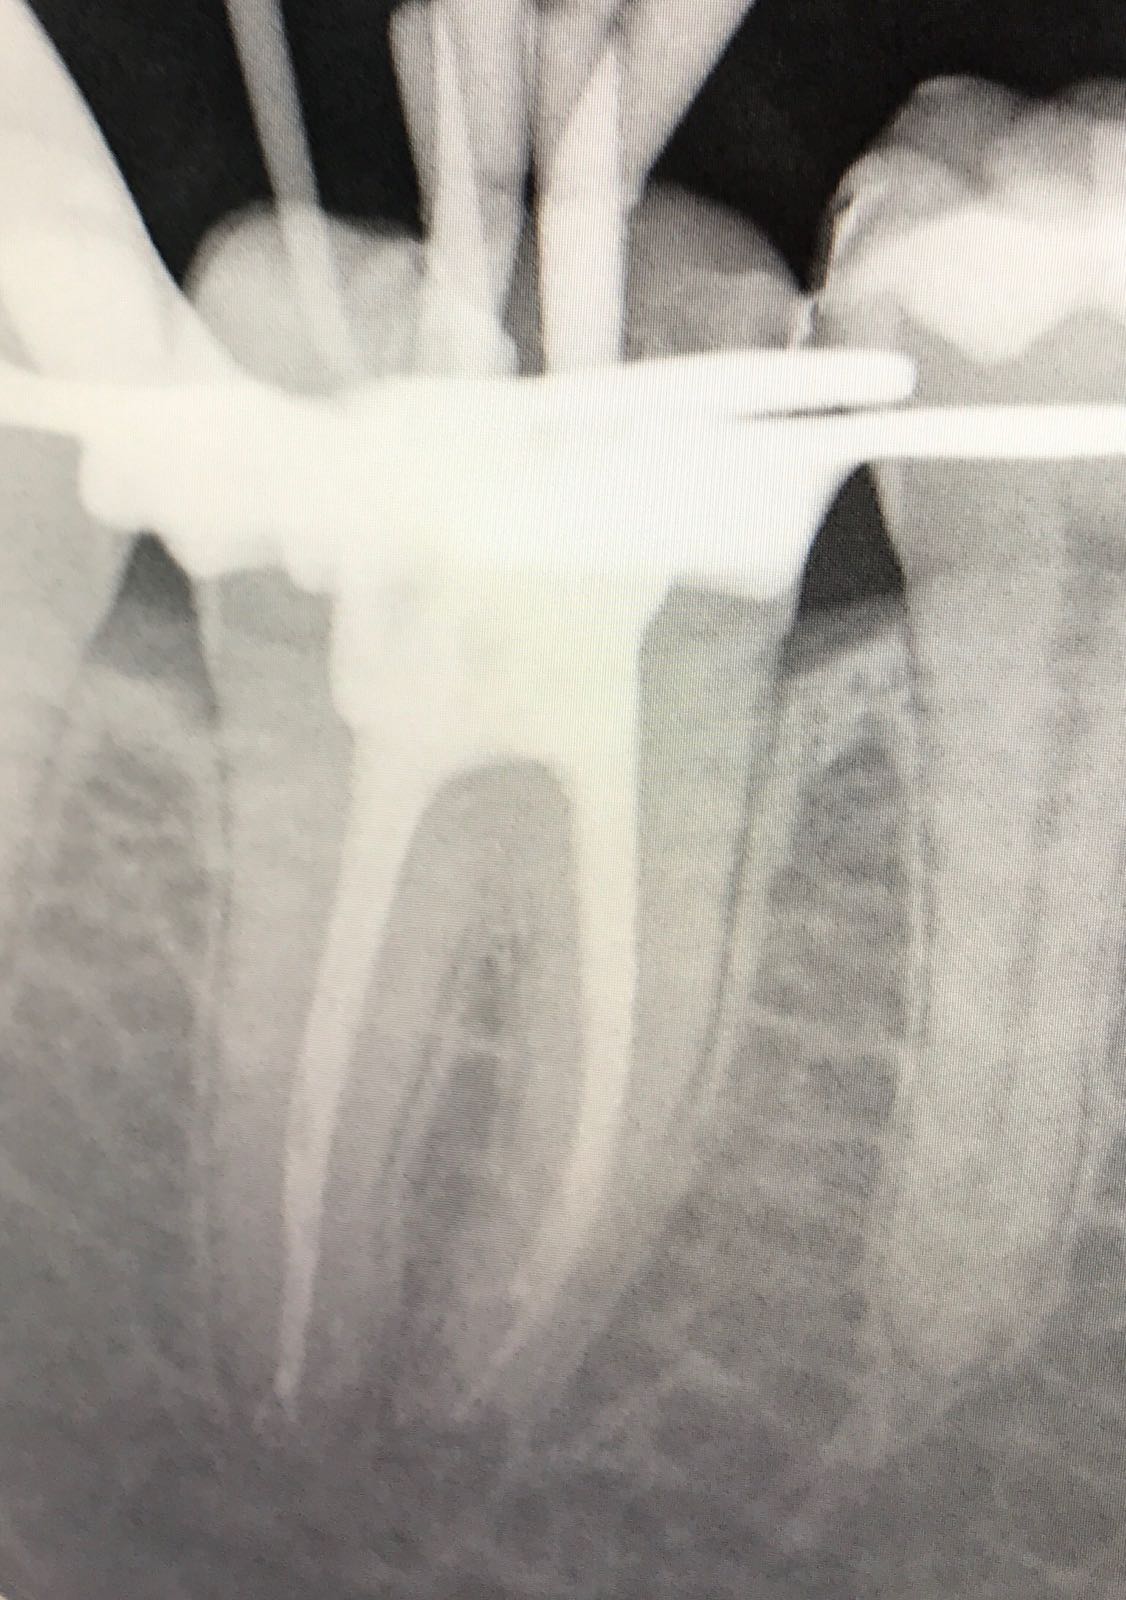

En la segunda fotografía, localizamos y realizamos la medición de los conductos.